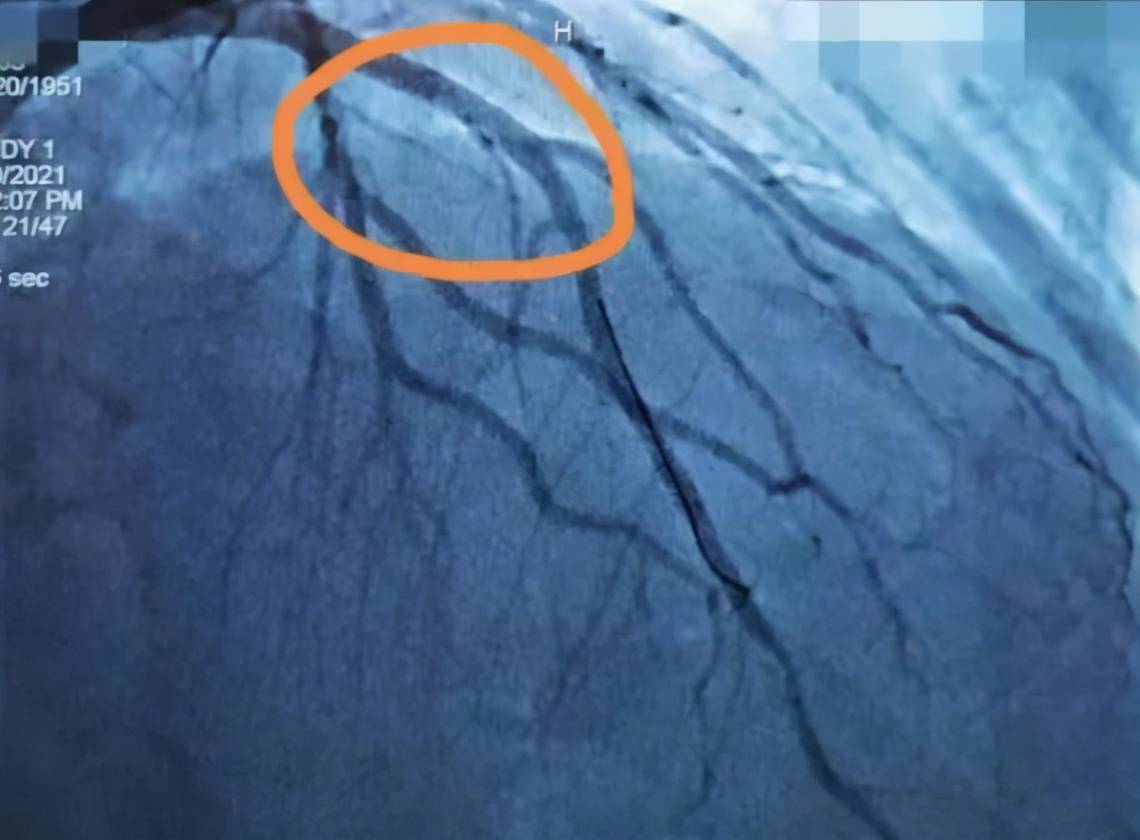

“大爷病情危重 , 造影显示 , 他其中一根心脏大血管有90%狭窄 , 同时伴有斑块破裂 。 ”回忆危急时刻 , 章永根主任也捏了一把汗 。